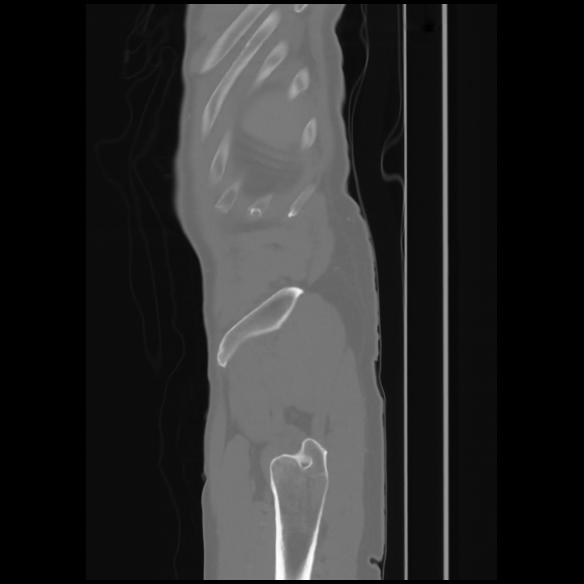

7 CUERPO,CE,Sagittal,3.000,CUERPO,Sagittal,